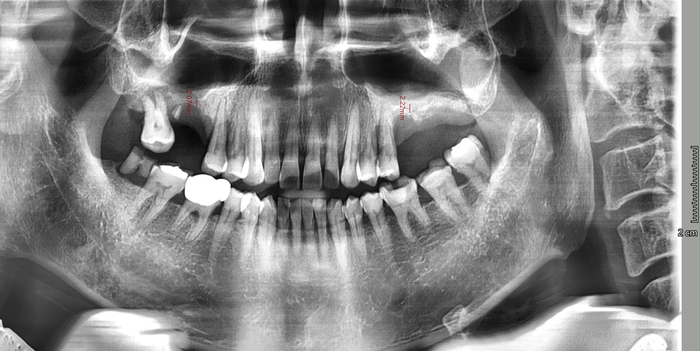

오랜 시간 치아가 방치되어 아래 파노라마와 같은 모습이었습니다.

엑스레이 사진에서 길이측정을 해보면 위쪽 어금니쪽에 뼈 수직길이가 2~3 미리 정도밖에 남지 않아

보통 심는 8~10미리의 임플란트를 심기위해 상악동수술(상악동거상술과 뼈이식)도 해야하는 상태였습니다.